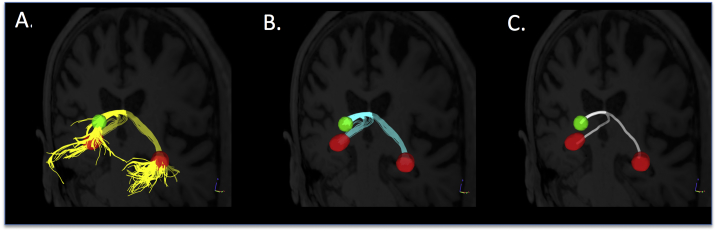

Fig. 3.

Demonstration of streamline tractography and reconstruction of continuous fornix bundles. In every participant's native diffusion space, A) streamline tractography (yellow streamlines) was performed using the spherical (green) and fimbriae (red) regions of interest as separate seeds and limited by a subject-specific region of avoidance (not shown). B) To enable group comparisons guided by anatomically-based landmarks, the portion of each streamline that extended beyond the ROIs was trimmed, keeping only that portion between the ROIs (cyan). D) Finally, the single streamline with the highest average fractional anisotropy (white streamline) was selected for each participant and used to extract quantitative metrics for statistical analyses. (For interpretation of the references to color in this figure legend, the reader is referred to the web version of this article.)